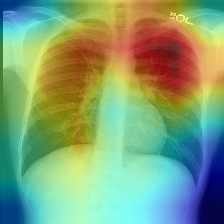

Disease classification relying solely on imaging data attracts great interest in medical image analysis. Current models could be further improved, however, by also employing Electronic Health Records (EHRs), which contain rich information on patients and findings from clinicians. It is challenging to incorporate this information into disease classification due to the high reliance on clinician input in EHRs, limiting the possibility for automated diagnosis. In this paper, we propose \textit{variational knowledge distillation} (VKD), which is a new probabilistic inference framework for disease classification based on X-rays that leverages knowledge from EHRs. Specifically, we introduce a conditional latent variable model, where we infer the latent representation of the X-ray image with the variational posterior conditioning on the associated EHR text. By doing so, the model acquires the ability to extract the visual features relevant to the disease during learning and can therefore perform more accurate classification for unseen patients at inference based solely on their X-ray scans. We demonstrate the effectiveness of our method on three public benchmark datasets with paired X-ray images and EHRs. The results show that the proposed variational knowledge distillation can consistently improve the performance of medical image classification and significantly surpasses current methods.

翻译:仅依靠成像数据的疾病分类吸引了对医学图像分析的极大兴趣。但是,目前的模型还可以通过采用包含关于病人和临床医生发现情况的丰富信息的电子健康记录(EHRs)来进一步改进。由于在EHRs中高度依赖临床投入,因此将这一信息纳入疾病分类具有挑战性,限制了自动诊断的可能性。在本文件中,我们提议了\textit{ varitional point squining} (VKD),这是基于X光的疾病分类的一个新的概率推论框架,它利用了EHRs的知识。具体地说,我们采用了一个有条件的潜伏变异模型,我们通过该模型将X光图像与相关EHR文本的变异后视镜调节条件的潜在的X射线图像的显示纳入疾病分类。通过这样做,模型获得了在学习期间提取与该疾病相关的视觉特征的能力,因此能够仅仅根据X光扫描结果对隐蔽病人进行更精确的推断。我们用三个公共基准数据集与配对X光图像和EHRs 的模拟方法证明了我们的方法的有效性。我们采用了一个有条件的隐隐隐隐隐隐性潜变量,从而能够持续地改进目前医学图像的成绩。结果,从而显示了拟议的变异性。